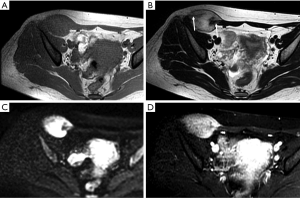

Endometriosis

The anterior abdominal wall is the most common site of extrapelvic endometriosis, which usually develops in a cesarean section scar, with a wide range of reported incidence rates of 0.03–3.5% (60). The most plausible cause of scar endometriosis is implantation of endometrial stem cells at the surgical site at the time of uterine surgery. Anterior wall endometriosis in patients with no prior surgeries is rare (61). Abdominal wall endometriomas are often the only manifestation of endometriosis with no associated pelvic endometriosis. The typical presentation is a female patient with cyclical pain from a mass in scar tissue (62).

The appearance of abdominal wall endometriosis on CT and MRI depends on the phase of the patient’s menstrual cycle, the chronicity of the process, the number of stromal and glandular elements, and the amounts of bleeding and associated inflammation (63). On CT, anterior abdominal wall endometriosis typically appears as a solid soft tissue mass that is hyperattenuated compared with muscle, although the attenuation can vary and be nonspecific. On MRI, it typically presents as a solid mass that is mildly hyperintense on both T1WI and T2WI as a result of subacute hemorrhage within the endometriotic crypts, although this finding may also vary (Figure 13). Mild to moderate contrast enhancement is present (60).